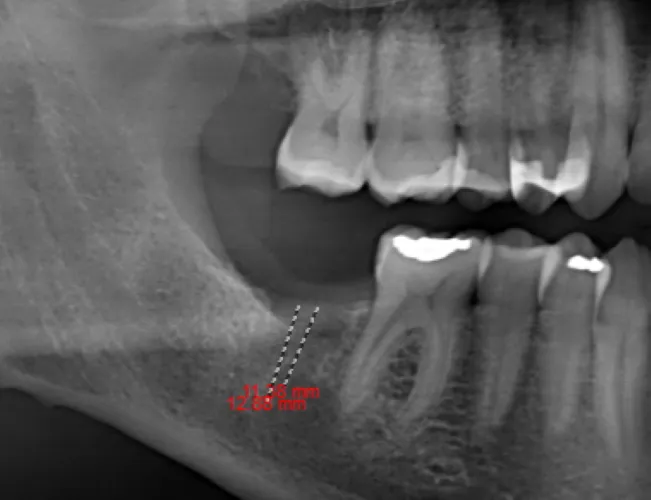

Dental implant bridges are a durable, long-lasting option for patients missing several teeth in a row. Unlike traditional bridges that rely on adjacent natural teeth for support, implant bridges are anchored securely to dental implants placed directly into the jawbone. This provides superior stability, preserves bone structure, and helps maintain your natural facial shape.

Each implant bridge is custom-crafted to match the color, size, and shape of your natural teeth, offering a seamless and aesthetic result. With implant bridges, you can enjoy a comfortable, secure bite and improved speech—without the worry of slipping or the need for adhesives.

This treatment is ideal for patients seeking a fixed, non-removable alternative to partial dentures, with the added benefit of protecting long-term oral health.